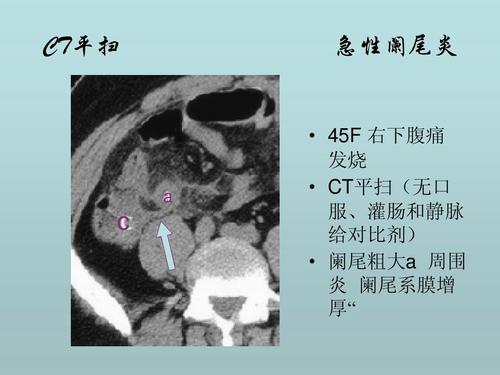

急性阑尾炎的ct表现

阑尾炎的ct诊断

急性阑尾炎的ct诊断,简单易懂!

【经典之作】正常阑尾和阑尾炎的ct表现

急性阑尾炎CT图片